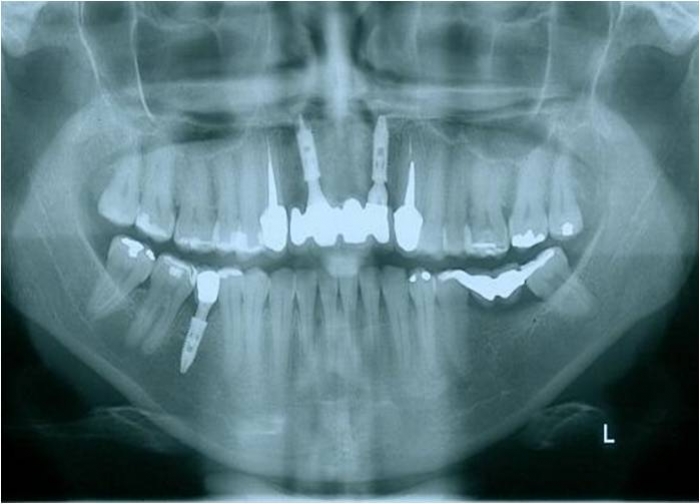

Raio x inicial

Raio x após enxerto ósseo